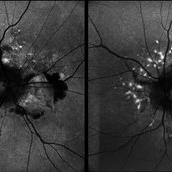

Both Eyes Fundus Autofluorescence in Case of CNVM with Angioid Streaks Both Eyes Fundus Autofluorescence in Case of CNVM with Angioid StreaksNov 29 2024 by Anand Temkar A 45 year old male came with chief complaint of blurring vision in right eyes since past 4 days. His vision is 6/12 in right eye and 6/9 in left eye. His vision was 14 mmHg in right eye and 16 mmHg in left eye. He was diagnosed with Angioid Streaks in both eyes about a year ago, then he developed choroidal neovascularization in his left eye 8 months ago, for which he received AntiVEGF injections x 3. Left eye is a stable eye now. Patient presented with right eye choroidal neovascularization in a case of Angioid Streaks on recent follow up. We have advised him right eye AntiVEGF injections x 3. In this image we can see fundus hypoautofluorescence in right eye due to hemorrhages and angioid streaks and in left eye fundus hypoautofluorescence is noted due to angioid streaks. Photographer: Dr.Anand Temkar- Retina Foundation, Ahmedabad Imaging device: Mirante Condition/keywords: Angioid Streaks, choroidal neovascular membrane (CNVM), fundus autofluorescence (FAF)